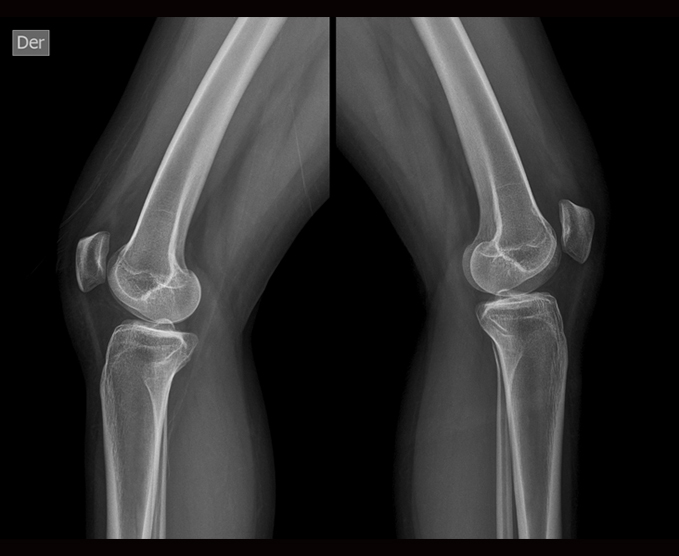

Radiología simple

Una radiografía es una prueba rápida e indolora que genera imágenes de las estructuras internas del cuerpo, en especial de los huesos.

- Rodilla